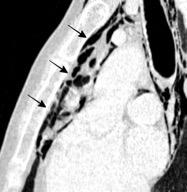

Líneas paraespinales formando un “paréntesis” por encima del diafragma. El signo señala el origen “intratorácico” de la lesión.

Conrad A et al. Pott’s disease associated with large and multiple abscesses in a 30-year-old migrant from Chad. BMJ Case Rep 2018

(lesiones toracoabdominales) La divergencia de las líneas paraespinales apunta a lesión toracoabdominal, que desde el tórax desciende y penetra en el abdomen.

Signo del “iceberg” positivo en Tb vertebral

Afectación por vía hematógena. Región dorsolumbar más frecuente. Afectación inicial: irregularidad de los platillos vertebrales, disminución del disco intervertebral con esclerosis ósea adyacente. Kim. Radiographics.2001